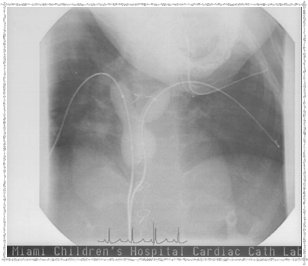

First Catheterization — Dr. Evan Zahn

In 2003, Elyse underwent a catheterization procedure at Miami Children's Hospital, performed by Dr. Evan Zahn. Below are some pictures that Dr. Zahn provided. She left the hospital the same day — remarkable!

Catheterization 2003 - Before

Before the procedure